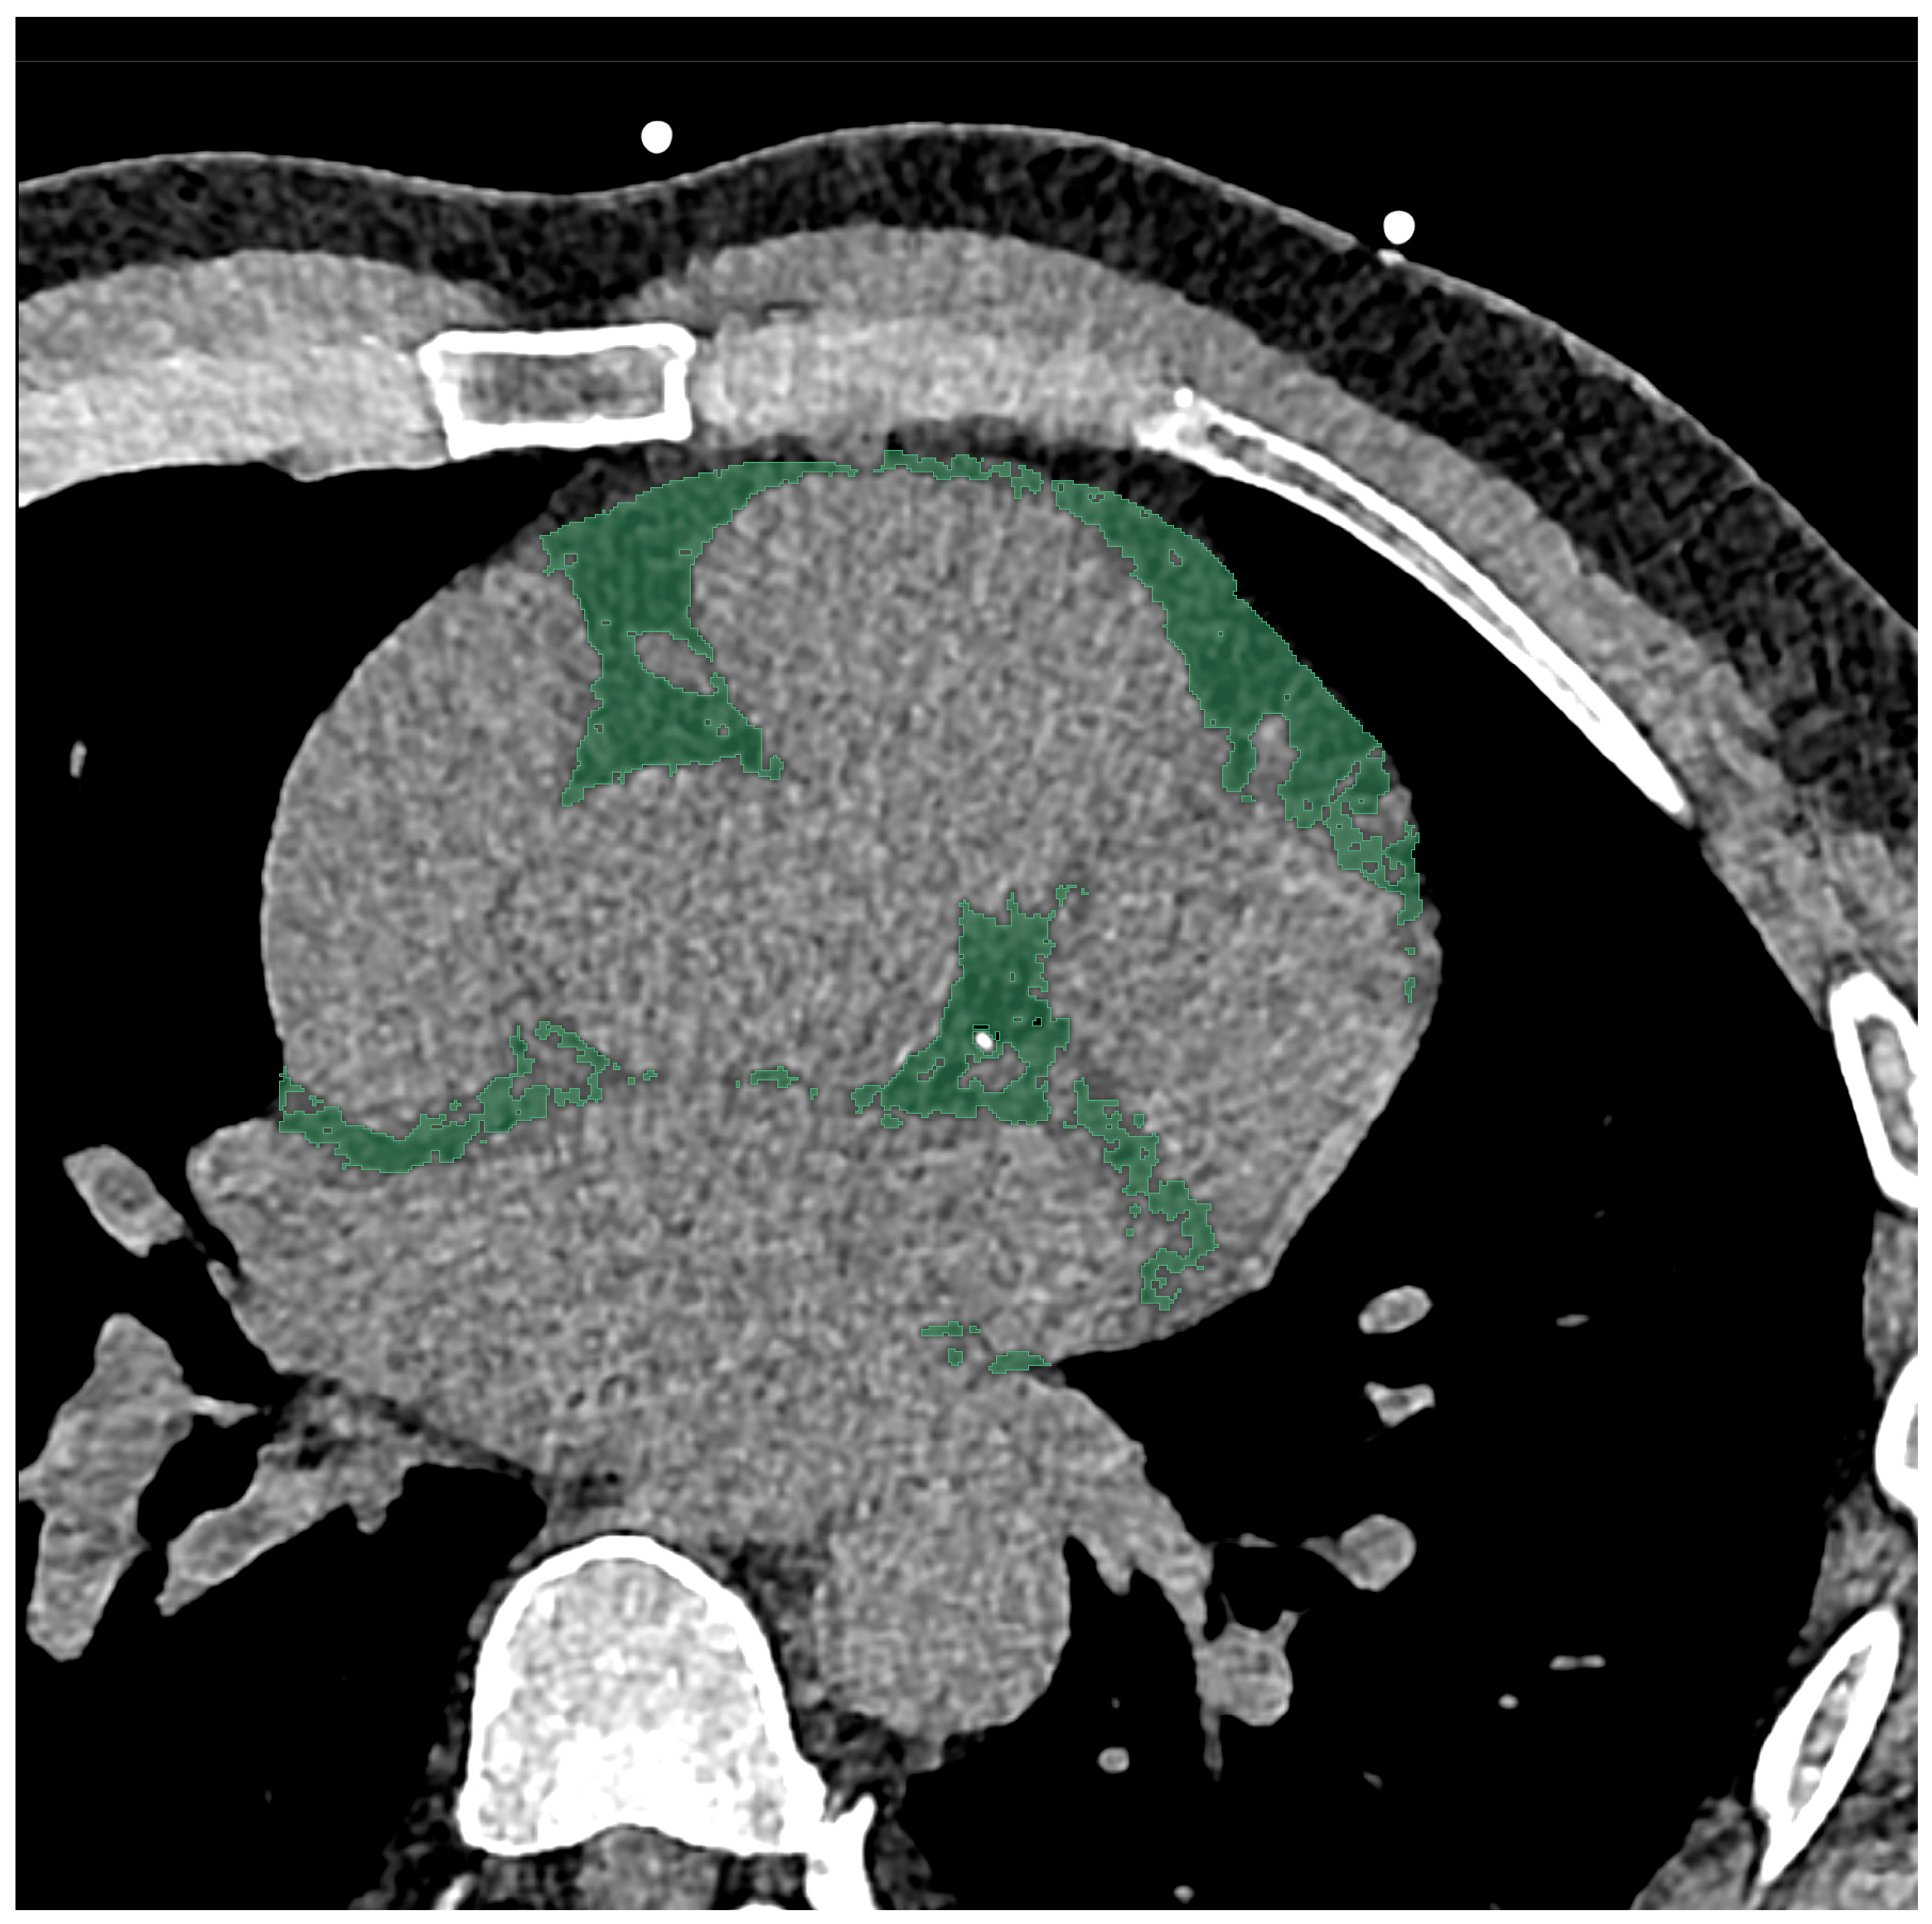

A soft vascular kernel (Bv40) was used to reconstruct axial non-contrast-enhanced images with a slice thickness of 2 mm (2 mm increment). The data was then anonymized, exported, and stored using digital imaging and communications in medicine (DICOM) format. For segmentation with a dedicated segmentation tool (3D Slicer, Version 4.11) [29], the aforementioned files were converted to the Neuroimaging Informatics Technology Initiative (NIFTI) format. EAT was segmented manually by a medical student and reviewed by a board-certified radiologist with 10 years of clinical experience in cardiovascular imaging and 6 years of experience in segmentation. The entire EAT was included in the segmentation, using a CT-attenuation threshold of −190 to −30 Hounsfield units (HU), in line with the literature [30]. The middle of the pulmonary trunk was used as a cranial border for the segmentation, with the caudal border being the contact of the apex and diaphragm. An example of segmentation is shown in Figure 1.

Figure 1.

Segmentation of the epicardial adipose tissue was performed on an axial view CT scan with a slice thickness of 2 mm. On this scan of a 55-year-old male, the area of segmentation is marked in green.